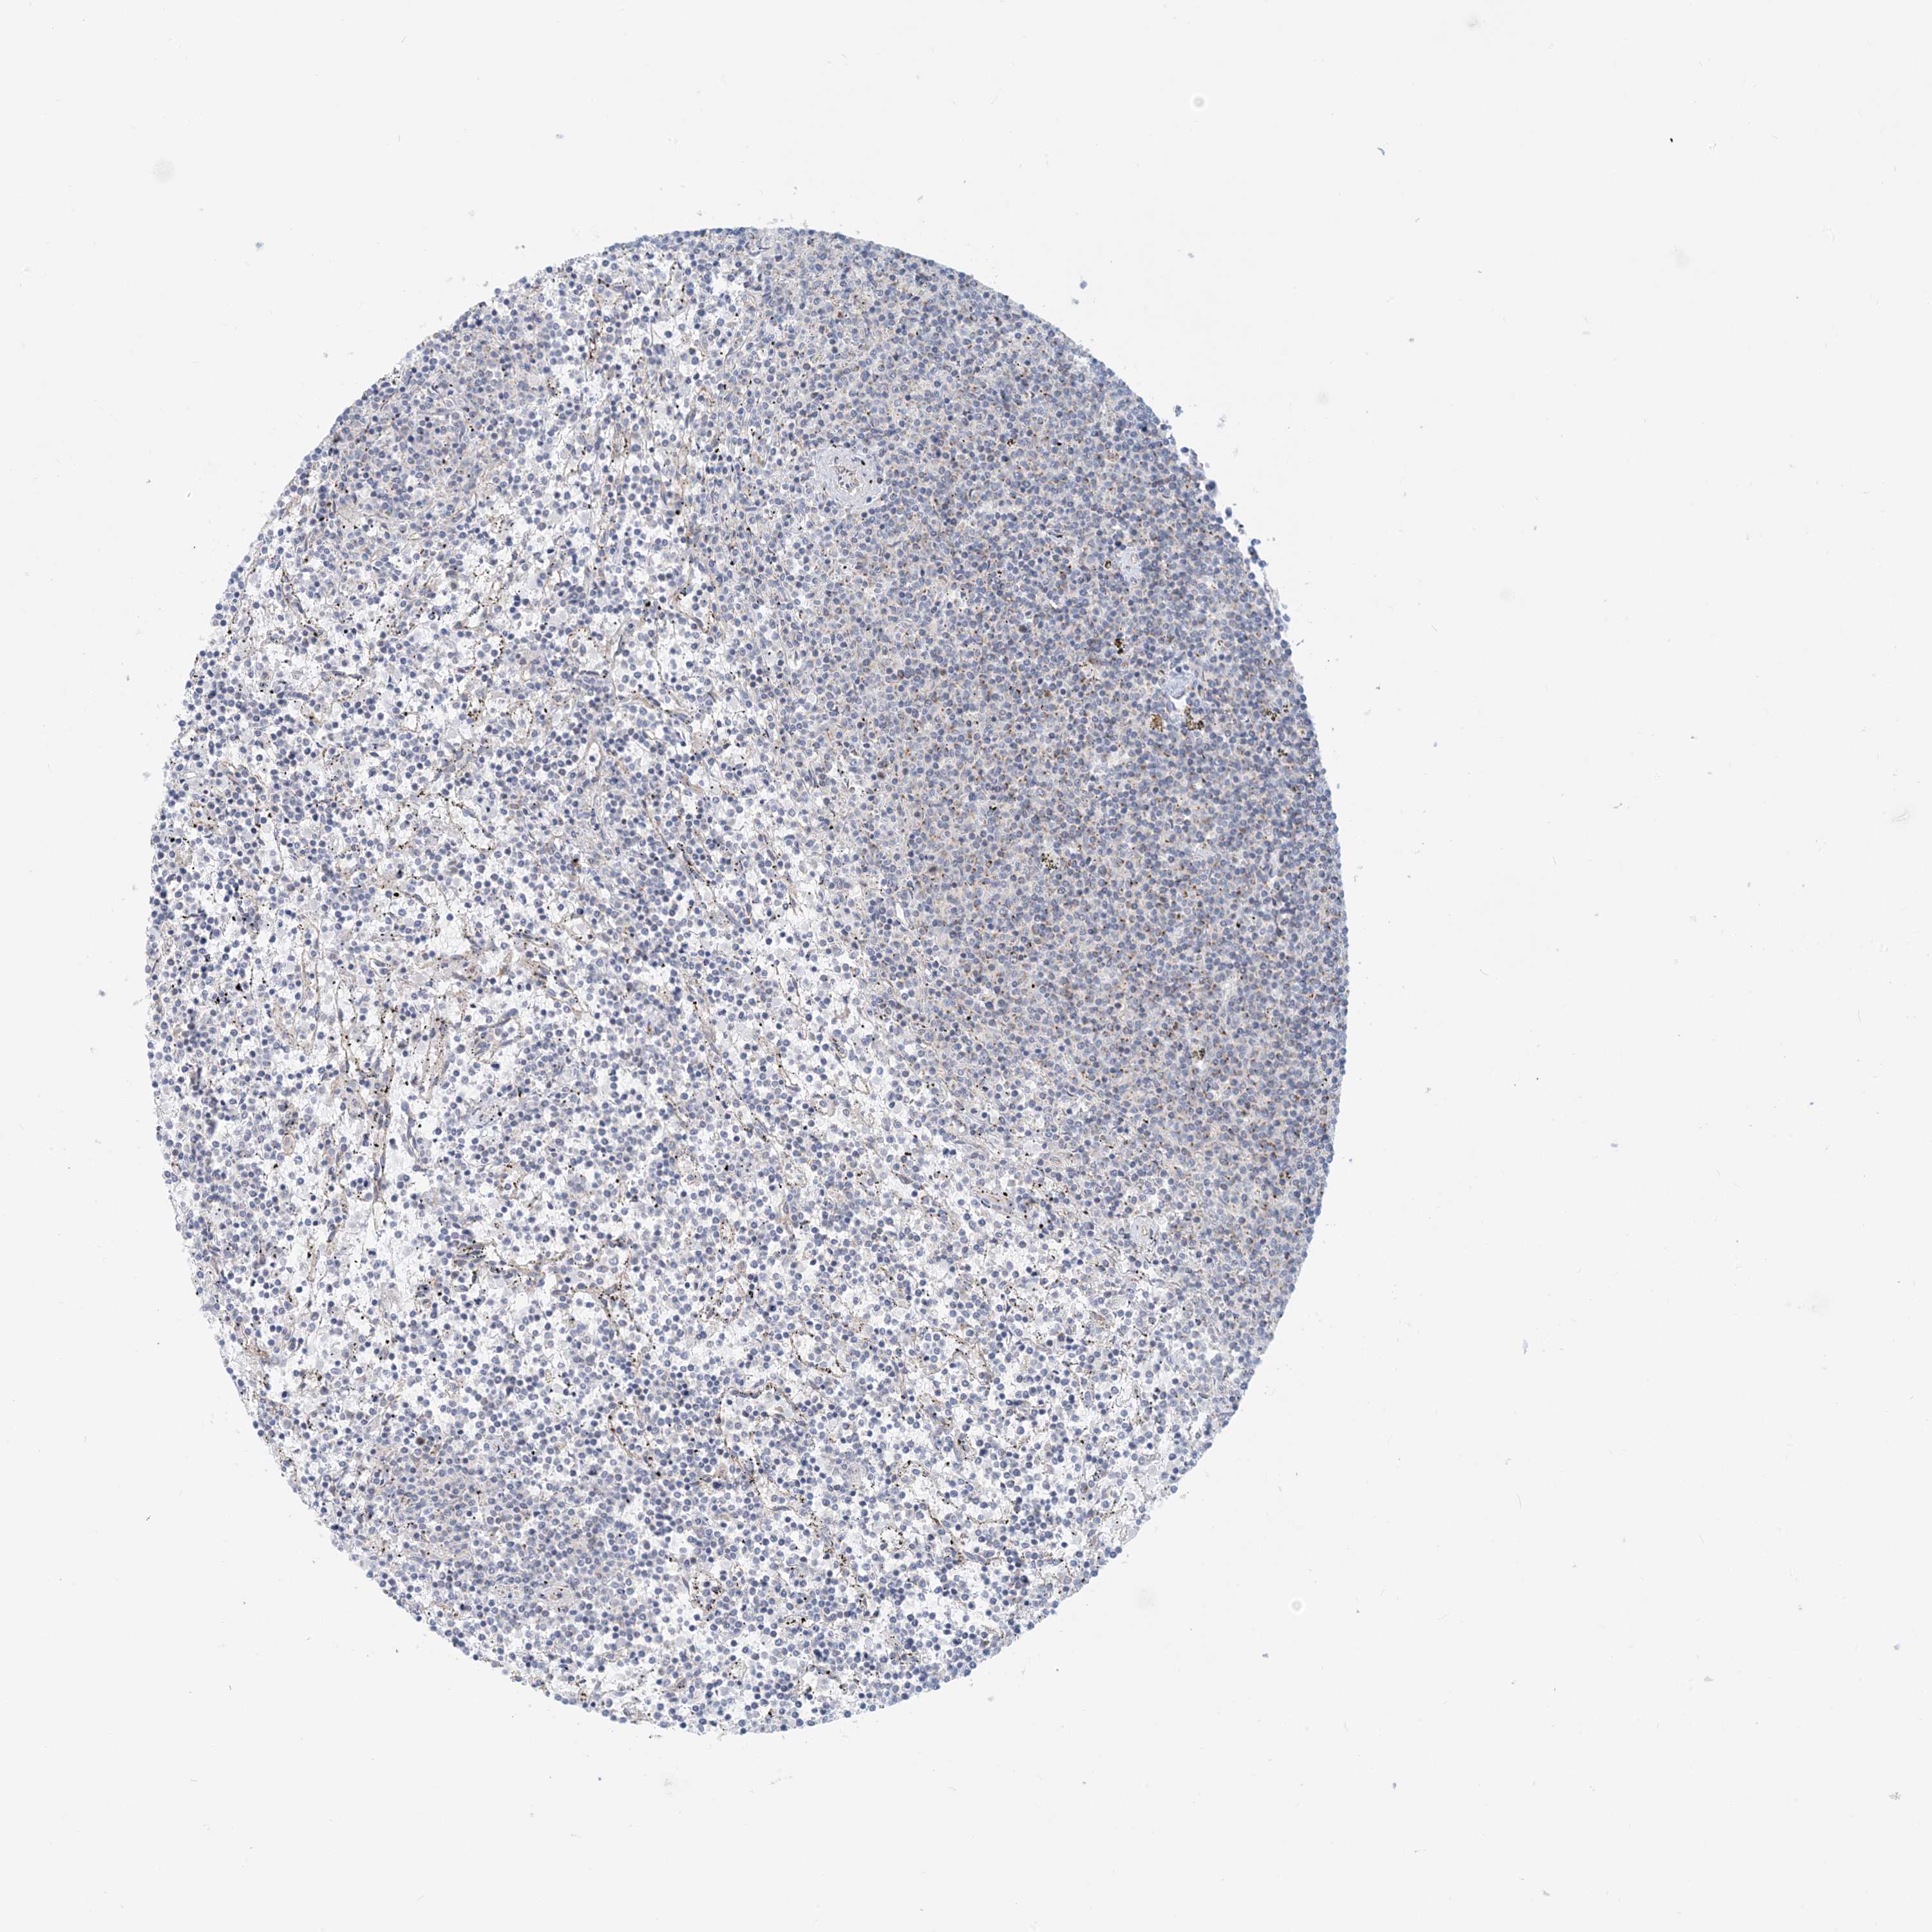

LYMPHOMA - Protein expressioni

A mouse-over function shows sample information and annotation data. Click on an image to view it in a full screen mode. Samples can be filtered based on level of antibody staining by selecting one or several of the following categories: high, medium, low and not detected. The assay and annotation is described here.

Antibody stainingi

Antibody staining in the annotated cell types in the current human tissue is reported as not detected, low, medium, or high, based on conventional immunohistochemistry profiling in selected tissues. This score is based on the combination of the staining intensity and fraction of stained cells.

Each image is clickable and will lead to virtual microscopy that enables deeper exploration of all samples and also displays staining intensity scores, fraction scores and subcellular localization as well as patient and tissue information for each sample.

Antibody HPA031966

Hodgkin's disease, NOS

Malignant lymphoma, non-Hodgkin's type, High grade

Malignant lymphoma, non-Hodgkin's type, Low grade